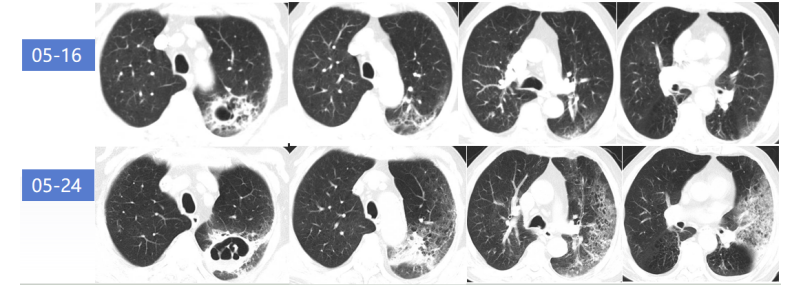

2023年5月24日多排CT胸部平扫CT所见:左肺上叶多发空洞,较前明显进展;右肺下叶支气管壁增厚伴条索影,两肺支气管旁多发絮状影及结节影,局部较前稍明显;左侧少许胸腔积液,伴左肺膨胀不全(图3)。